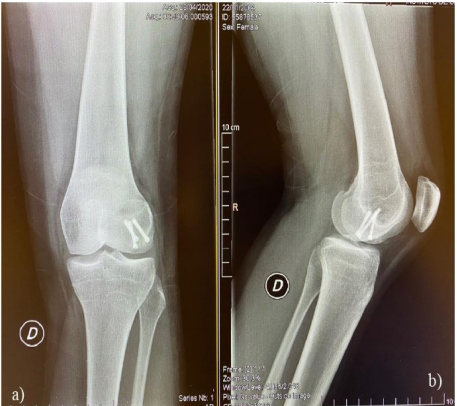

A los 54 meses de follow up la paciente presentaba un International Knee Documentation Committee (IKDC) de 100. Este es un score subjetivo, que evalúa 3 parámetros principales; la sintomatología, los deportes y las actividades de la vida diaria, a través de 18 ítems que utilizan una escala numérica, lo que genera valores de 0 a 100 puntos. Correspondiendo 100 puntos a una rodilla sin limitación. Este es el caso de nuestra paciente (Figura 4).

En el post operatorio no se utilizaron dispositivos de inmovilización, se permitió la deambulación con el uso de muletas sin cargar peso sobre el miembro operado por 6 semanas, se comenzó la movilización en forma precoz y la fisioterapia a las 4 semanas. A partir de la sexta semana se permitió la carga asistida en forma progresiva. A las 8 semanas la paciente deambulaba sin asistencia. A los 6 meses de la cirugía la paciente se presentaba asintomática, retomando en forma progresiva la actividad física. A 54 meses de la cirugía la paciente practica actividad física en forma diaria, cursando el Liceo Militar, sin presentar ninguna sintomatología a nivel de su rodilla.